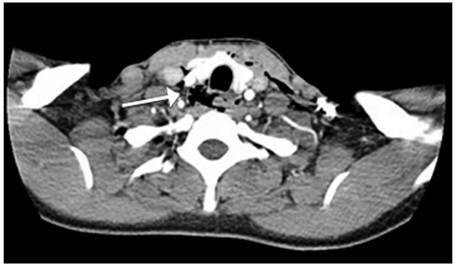

Ante la sospecha clínica de lesión vascular cervical como primera posibilidad, se tomó una radiografía de tórax postero-lateral que descartó la presencia de neumotórax, hemotórax u otra complicación (figura 3). Se realizó un angiotac cervical con contraste endovenoso, encontrando enfisema subcutáneo en los tejidos blandos, con solución de continuidad (figura 4) y una lesión en el tercio medio de la tráquea, con compromiso de su pared lateral derecha (figura 5), sin poder descartar una lesión del esófago en su segmento cervical. No se observó compromiso vascular ni óseo.